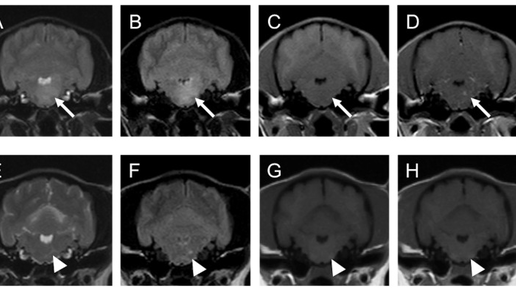

МРТ-Характеристики Лимфом Головного Мозга у Кошек и Собак

МРТ-Характеристики Лимфом Головного Мозга у Кошек и Собак Лимфомы центральной нервной системы (ЦНС) у собак и кошек встречаются относительно редко. Первичная лимфома ЦНС (PCNSL) – это опухоль, исходящая из тканей мозга/спинного мозга или оболочек, без признаков системного поражения на момент диагностики. У собак на PCNSL приходится около 4% всех лимфомmdpi.com и примерно 3–5% первичных внутричерепных опухолейmdpi.com. У кошек первичные лимфомы ЦНС еще более редки (менее 3% всех первичных опухолей ЦНС)mdpi...